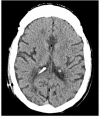

Complications related to Ventriculoperitoneal shunt placement are common, and multiple. Among them blockage and infection. We report a case of 44 years old man admitted to our hospital after an obstruction of his ventriculo-peritoneal shunt by an air bubble that caused behavioral problems and confusion. The patient was operated twice, the last time the puncture point had to be changed. The follow up was marked by a clear clinical improvement. Shunt malfunction continues to be a common neurosurgical problem in patients with shunted hydrocephalus, often leading to frequent and sometimes lengthy hospital stays. This case illustrates the management of this rare situation causing air bubble shunt obstruction.